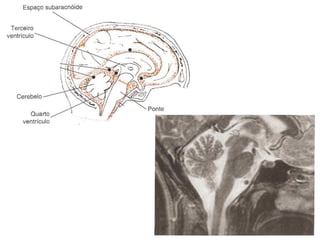

Ressonância Magnética do Crânio

• Sistema de obtenção de

imagens é mais sensível à

natureza molecular dos tecidos;

• Alta densidade tissular não

resulta em resolução de

contraste.

   Doenças da substância branca;

   Neoplasias;

   Doenças infecciosas;

   Distúrbios hemorrágicos;

   Distúrbios isquêmicos.

Tálamo

Hipotálamo

Hipófise

4º ventrículo